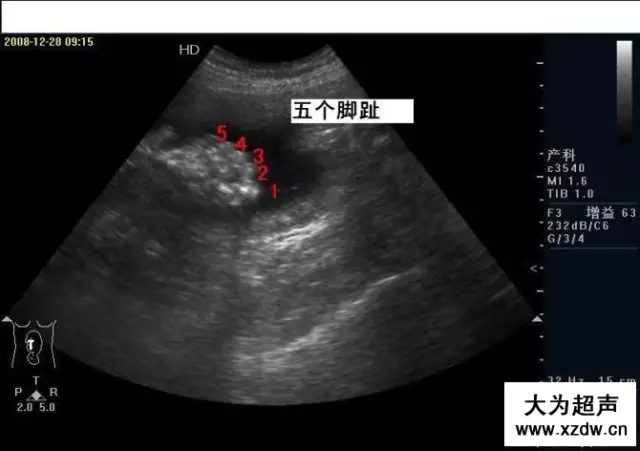

產(chǎn)科超聲正常圖片